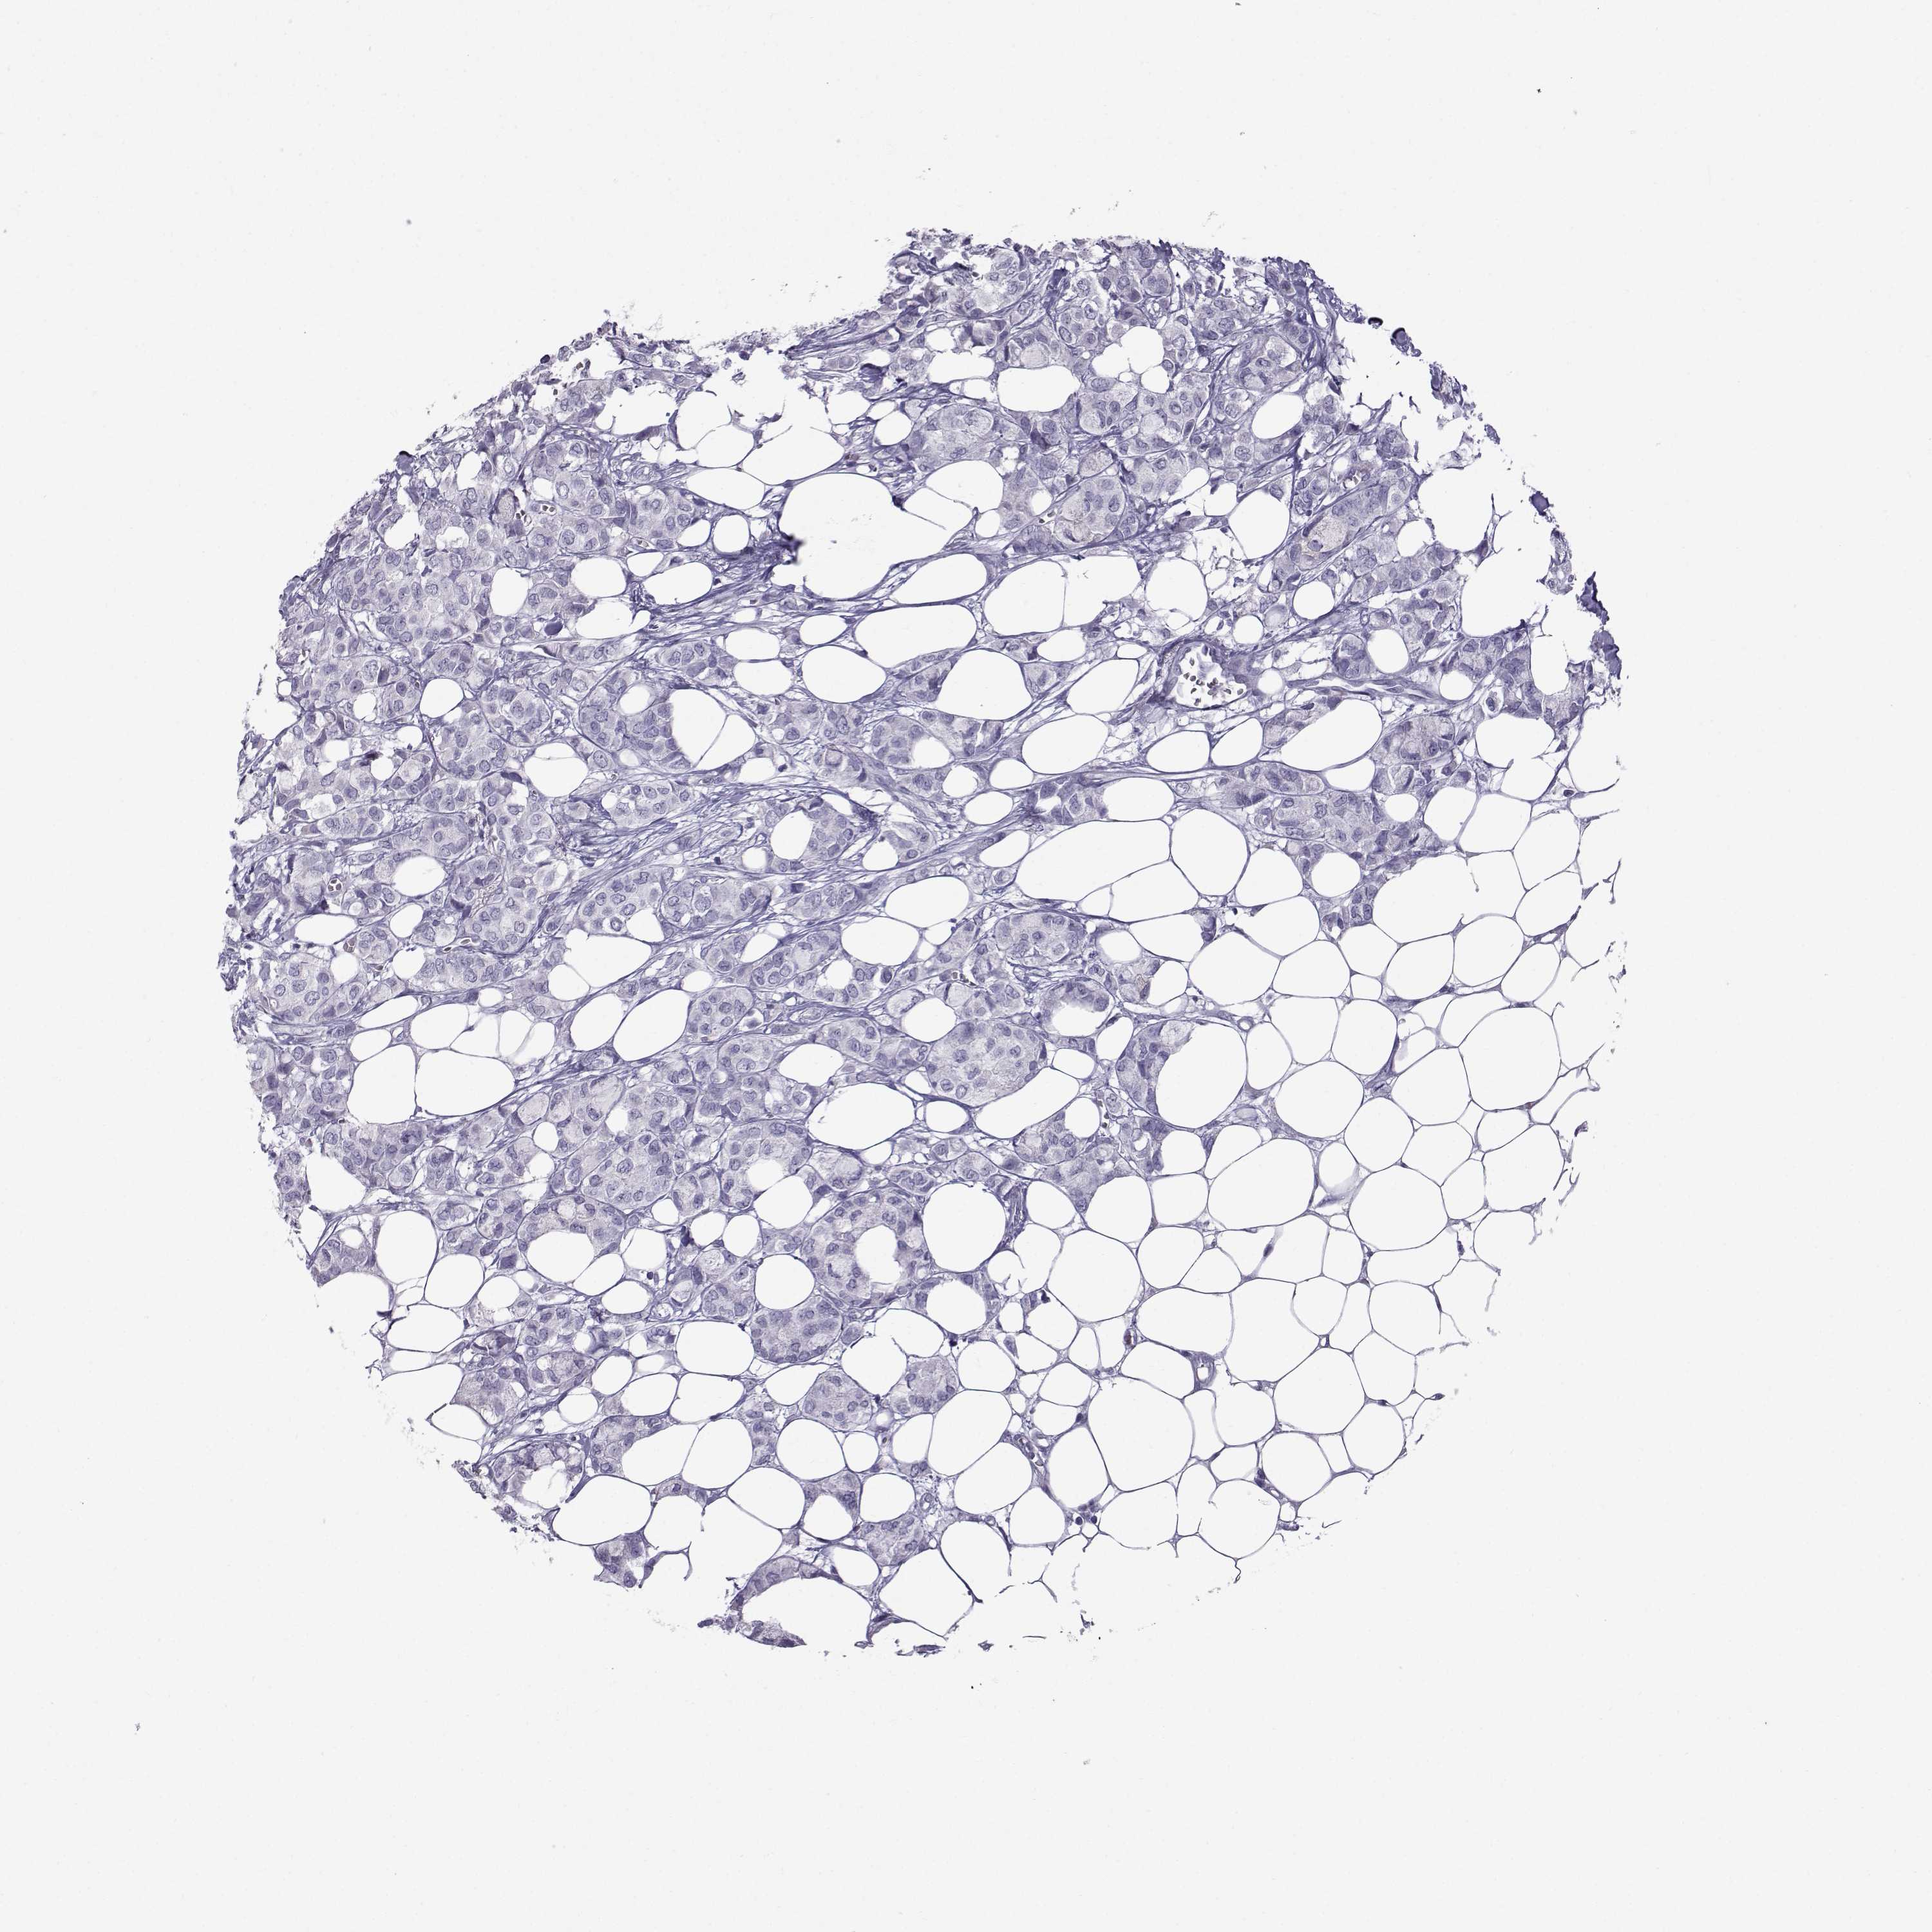

Breast cancer

Human cancer